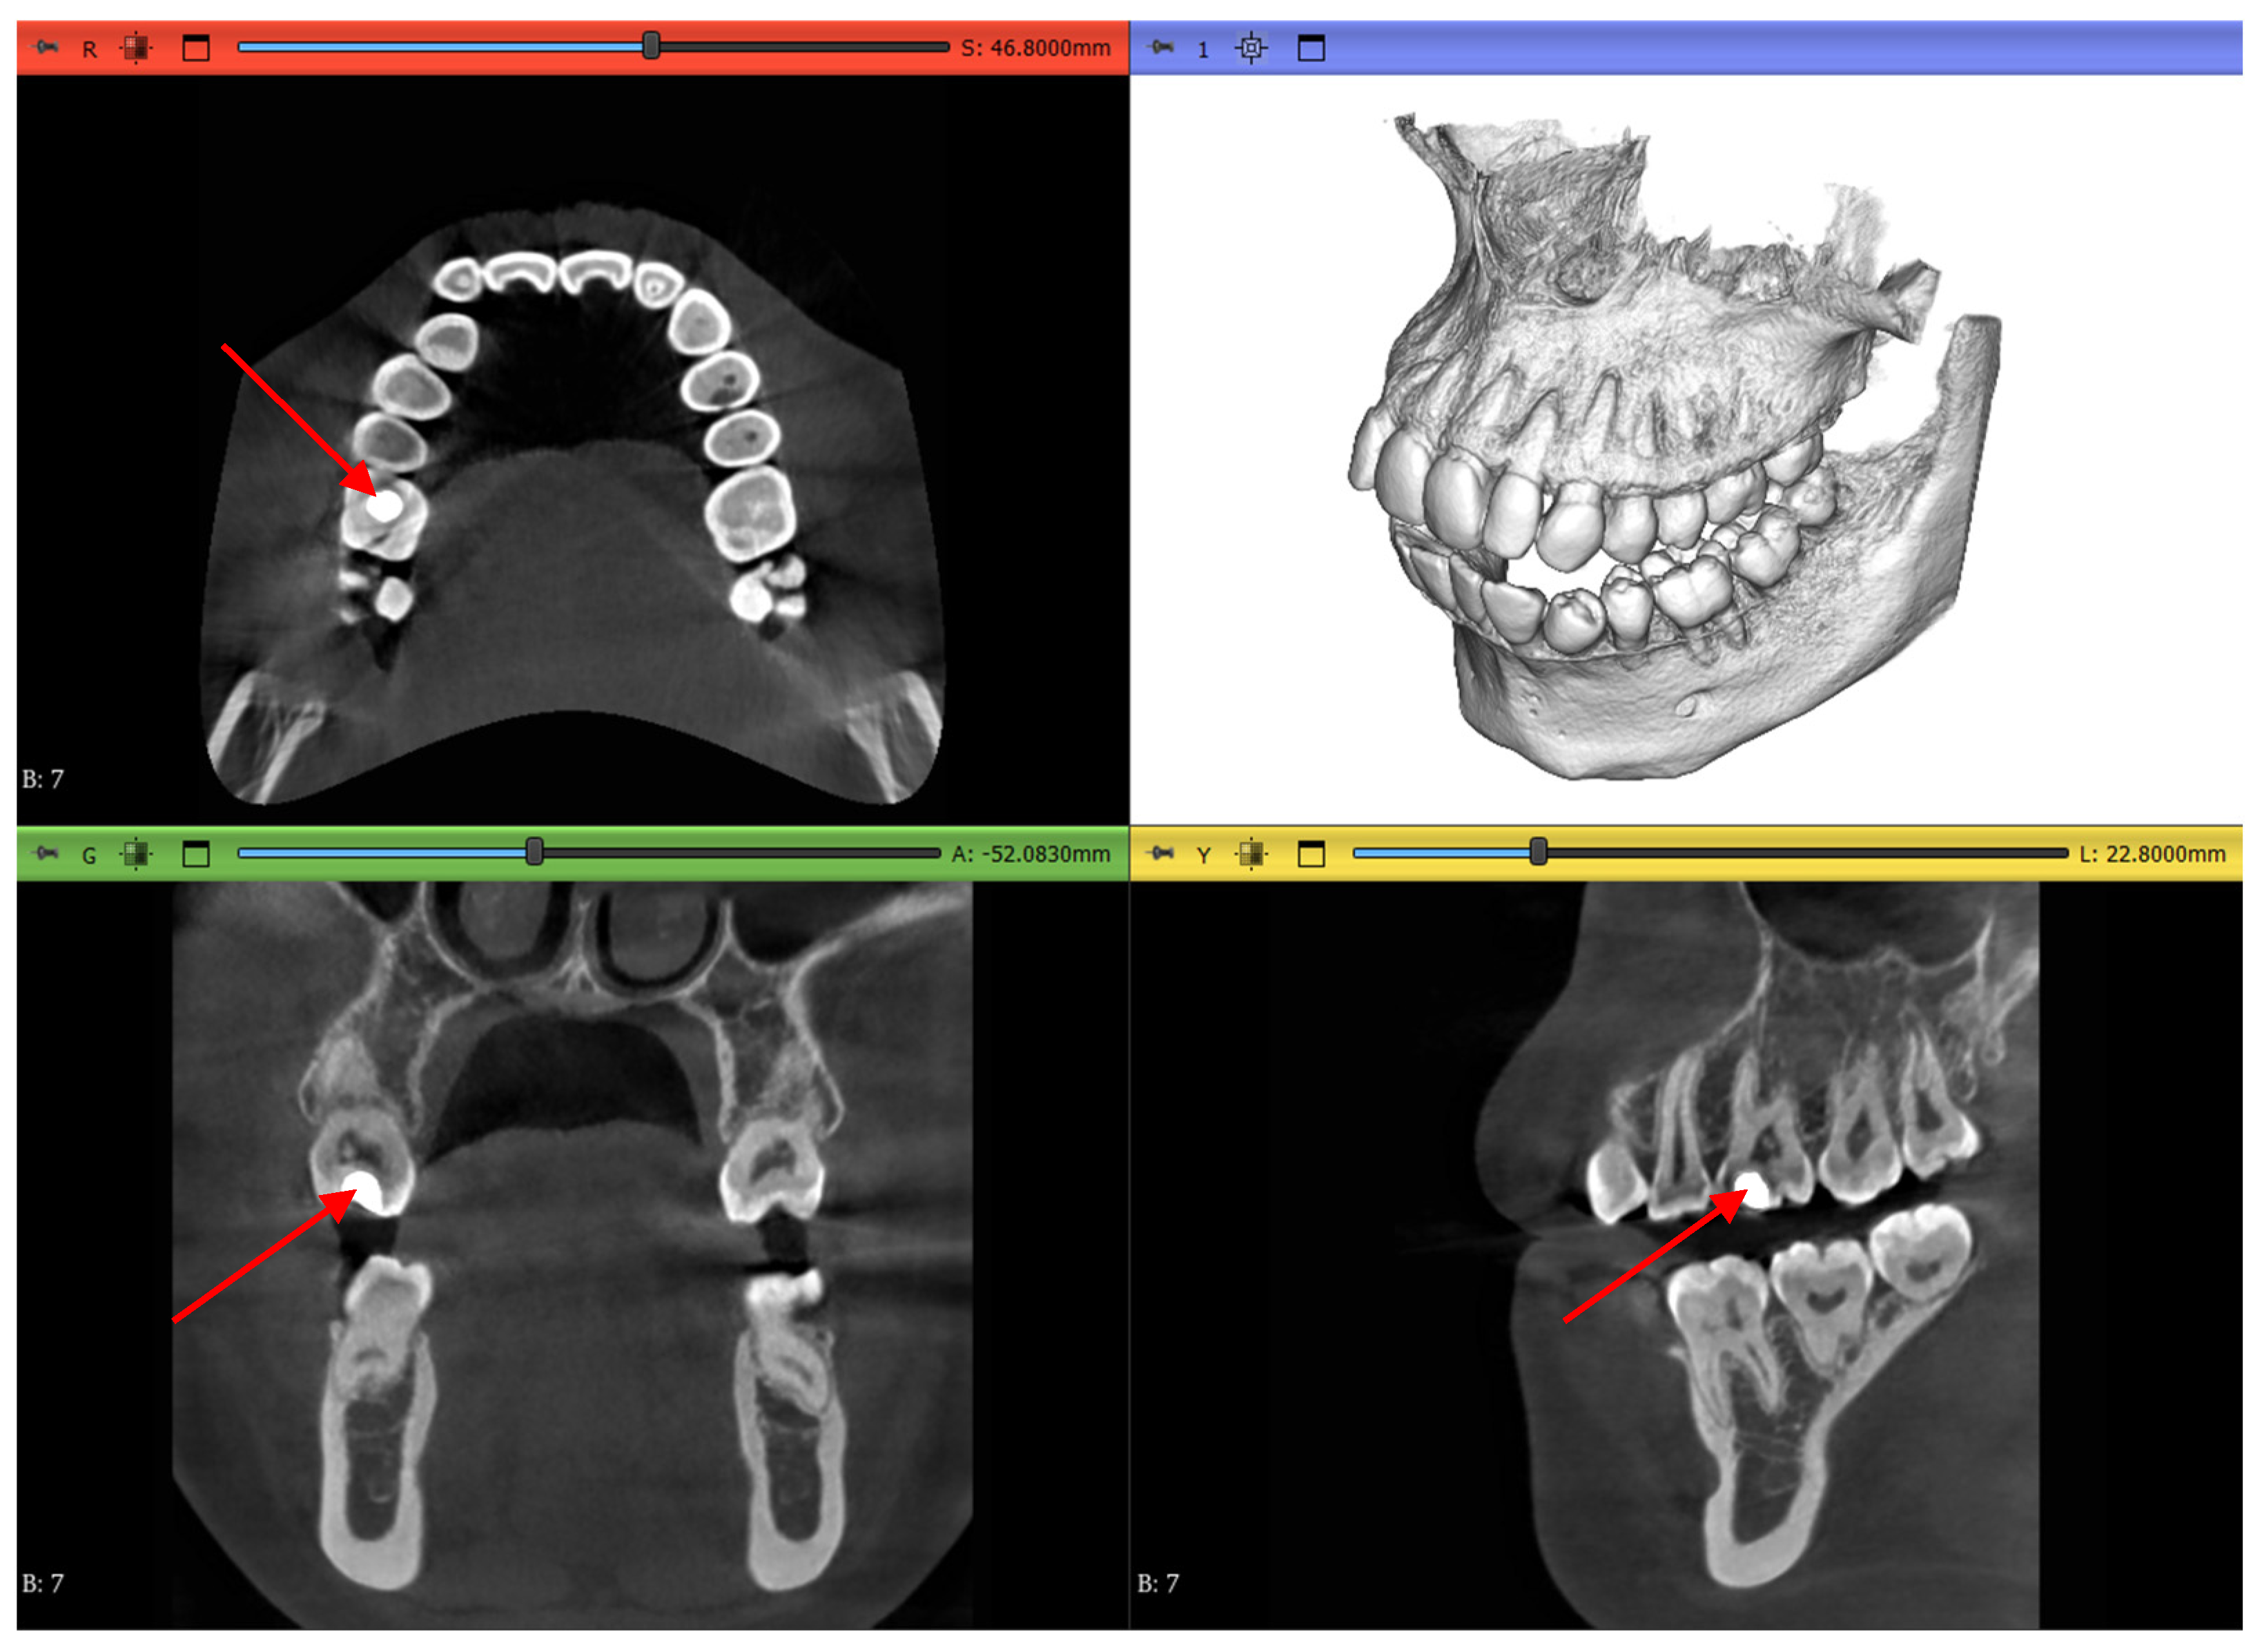

2.1. Datasets

2.3.1. Volume Cropping